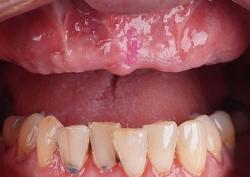

Примеры протезирования зубов

Каждый день мы помогаем восстанавливать улыбку нашим пациентам.